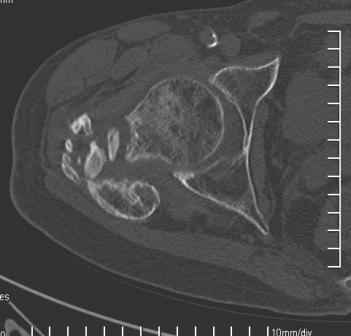

Больной Н. 44 года травма 1,5 года назад июнь 2008 года чрез-под вертельный перелом правого бедра. Во время лечения у больного развился алк. делирий, проводилось консервативное лечение перелома.

Беспокоят боли, укорочение конечности.Укорочение 3 см. Ногу поднимает, сгибание ограничено, ротационные движения в полном объеме.На КТ перелом сросся за счет костной мозоли.Что делать?

Протез? Если «да» Можно ли обойтись стандартной ножкой Corail?

Или межвертельная остеотомия?

Уважаемый Глеб, боли из-за ложного сустава шейки бедра. Сращения там нет.

Тазобедренный сустав сохранный и возраст пациента позволяет побороться. Согласен с Максимом, попробуйте остеотостеотомию.